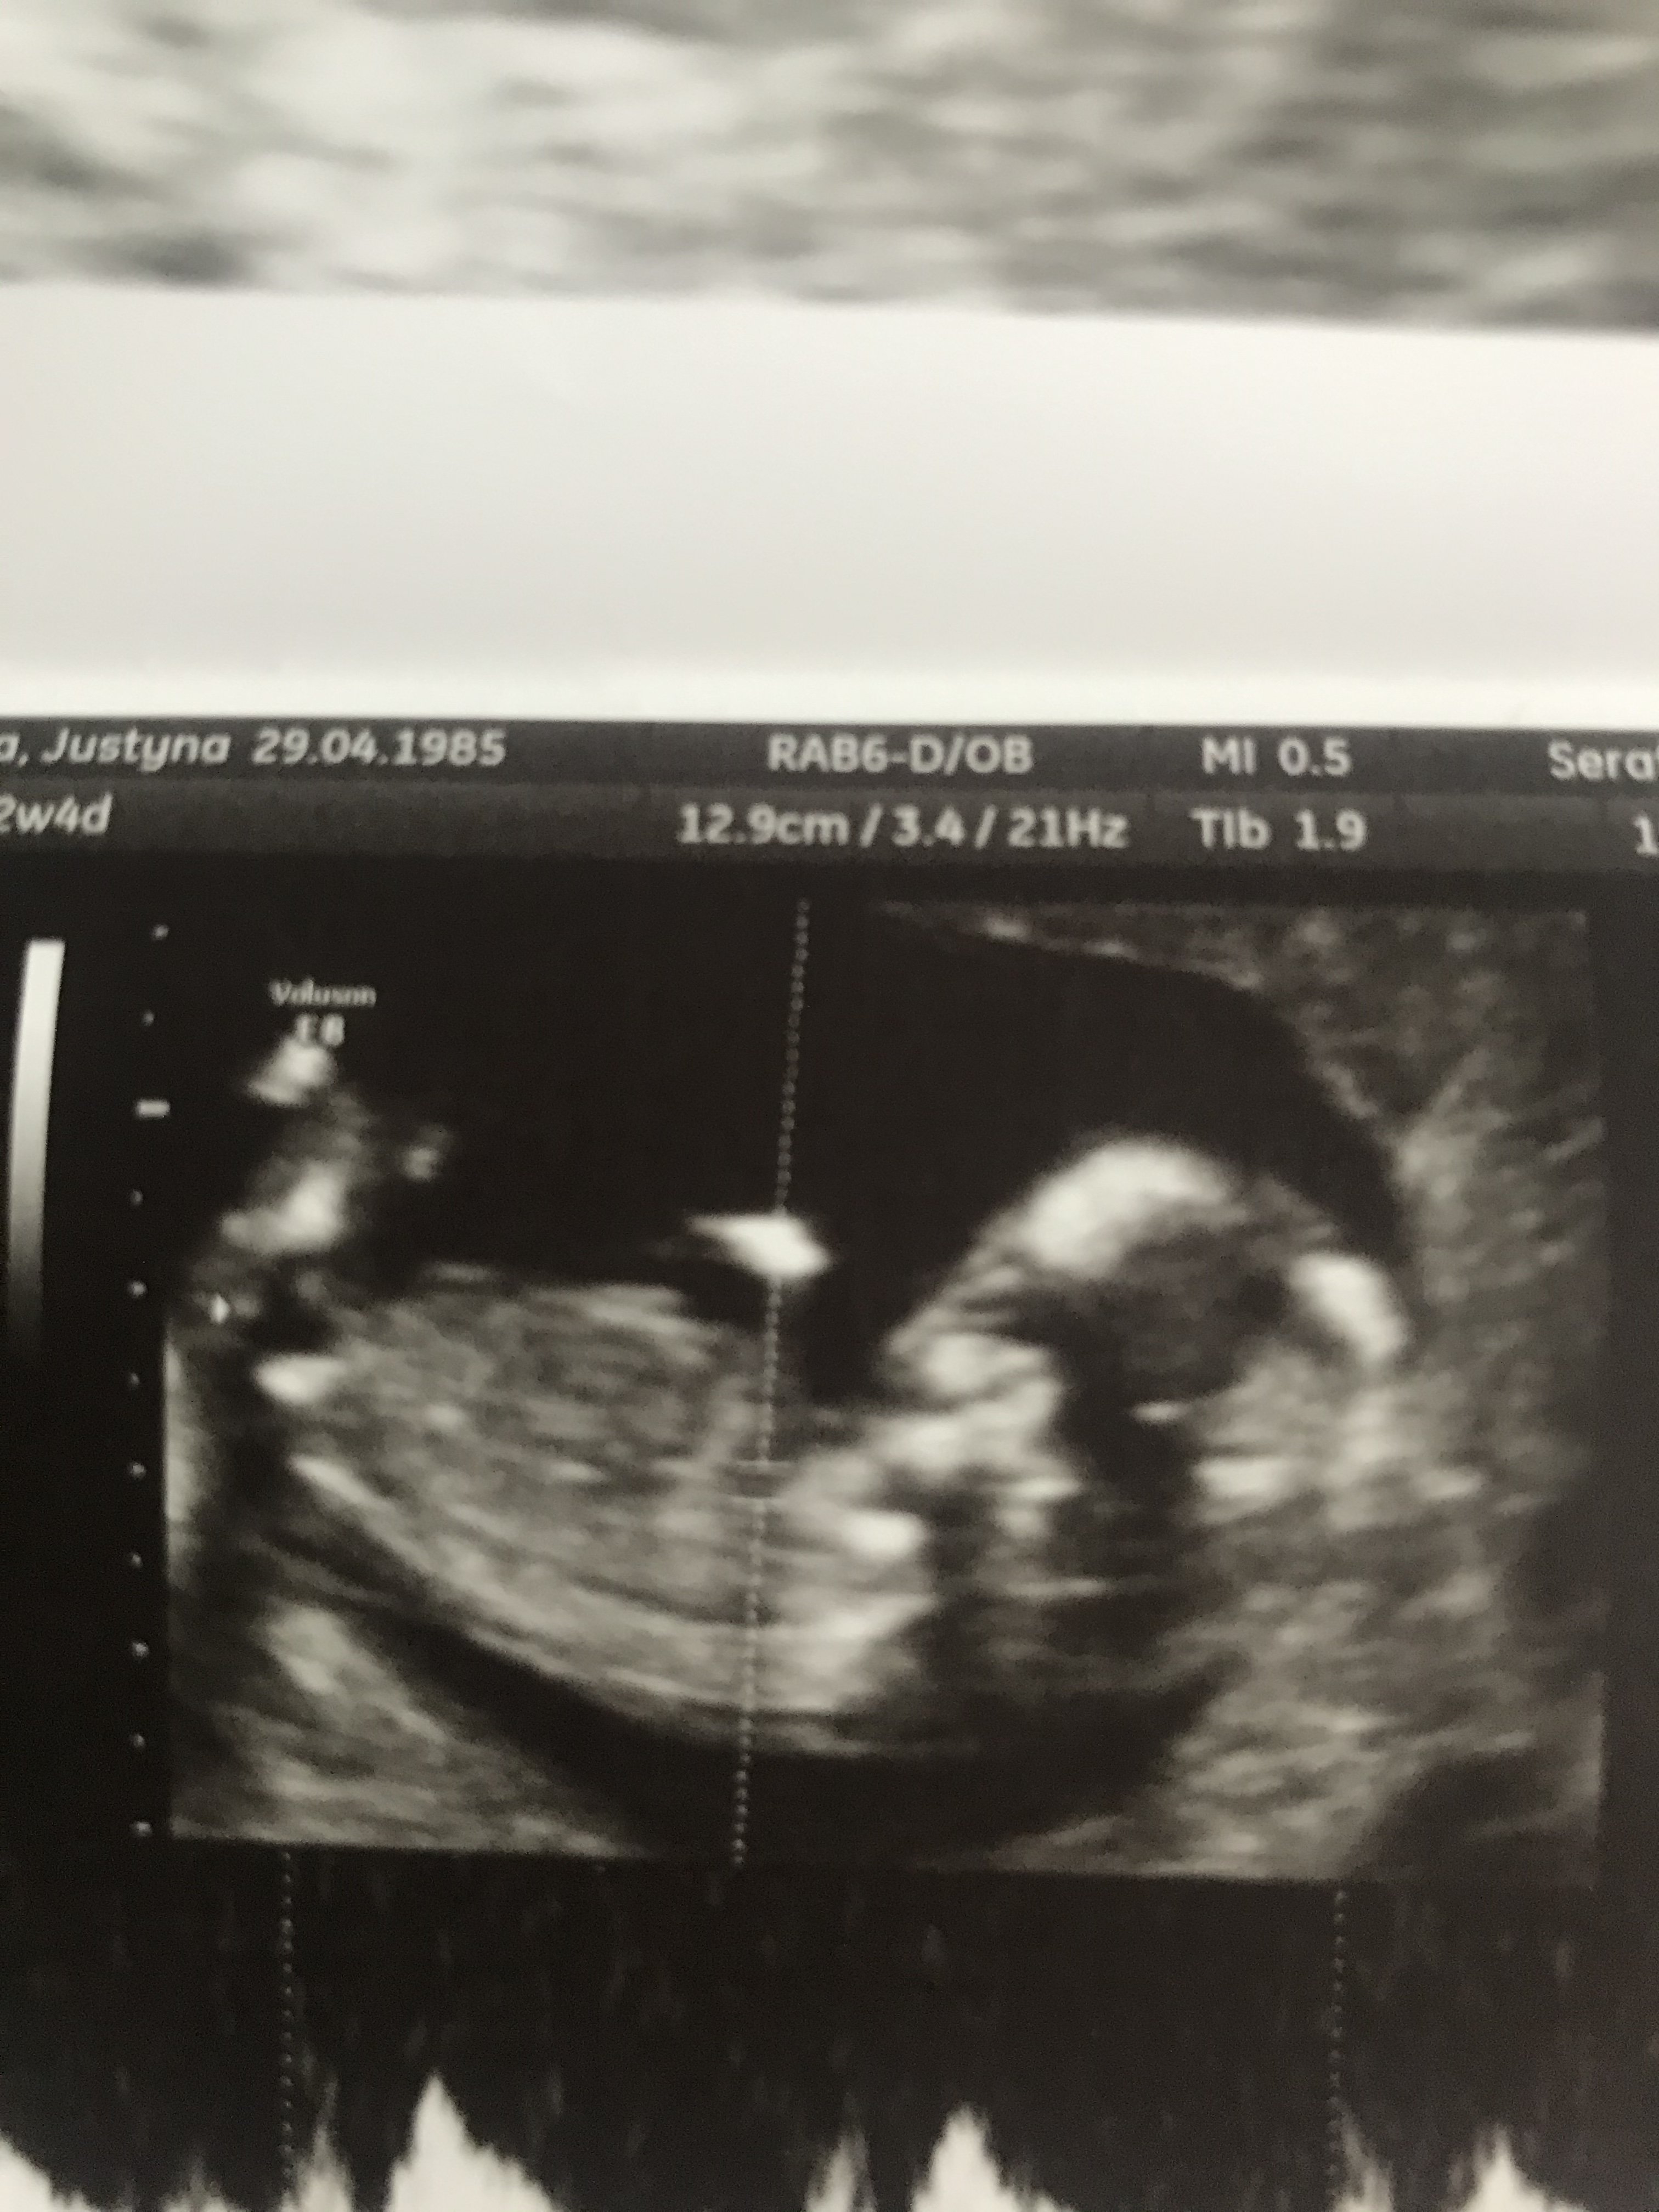

Pokaże Wam swoje zdjęcie z 12w4d. Dzidzia leży, ale ciężko mi dojrzeć nuba. Bo nie wiem czy to ręka, noga gdzieś nie zachodzi. Lekarz nic nie mówił. W pierwszej ciąży po pierwszych prenatalnych miałam mieć na 97% chłopca a jestem mama dziewczynki ;). Także ciekawa jestem czy teraz będzie upragniona siostra dla córki czy wyczekiwany syn dla męża ;).